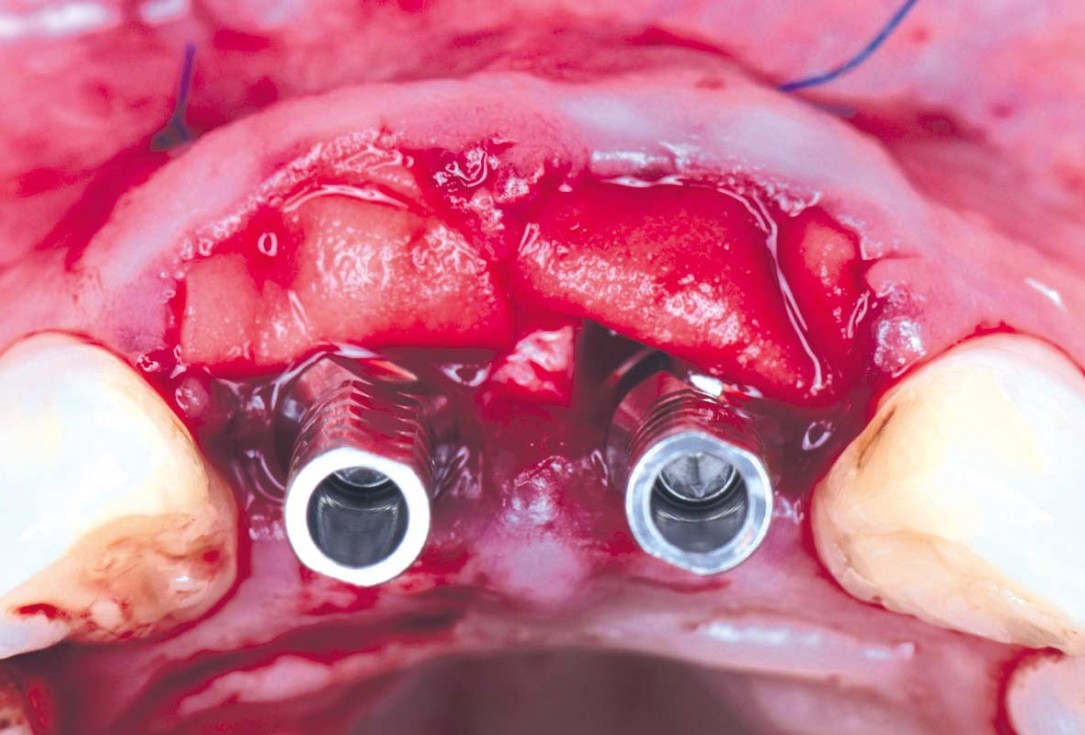

05/22 - Immediate implants are placed after extraction and the gap is filled with cerabone®cerabone® and mucoderm® for immediate implantation in the aesthetic area - Dr. D. Robles